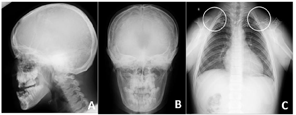

,反覆盖10mm,双侧尖牙及磨牙近中关系;51、61扭转,上颌牙弓狭窄,腭盖高拱,31、41间可见间隙约5mm(图2)。(3)影像学检查:①曲面断层片示多数乳牙滞留,恒牙迟萌,多颗埋伏阻生多生牙。54、64远中邻面低密度影及髓,牙根吸收(图3);②CBCT示全口恒牙排列紊乱,上下颌骨内可见13颗多生牙,均位于恒牙胚舌腭侧,形态类似相邻恒牙胚(图4);③头颅侧位片示头颅侧位片示上颌骨发育不足(NA-Apo:-5.9°),下颌前突(SNB: 98.2°;FH-NPo:90.0°),骨性III类错

畸形(ANB:-5.1°;FMA:31.0°)(图5)(表1);④头颅正位片示颅缝轻微增宽;⑤胸片示双侧锁骨远心端发育不足(图6)。